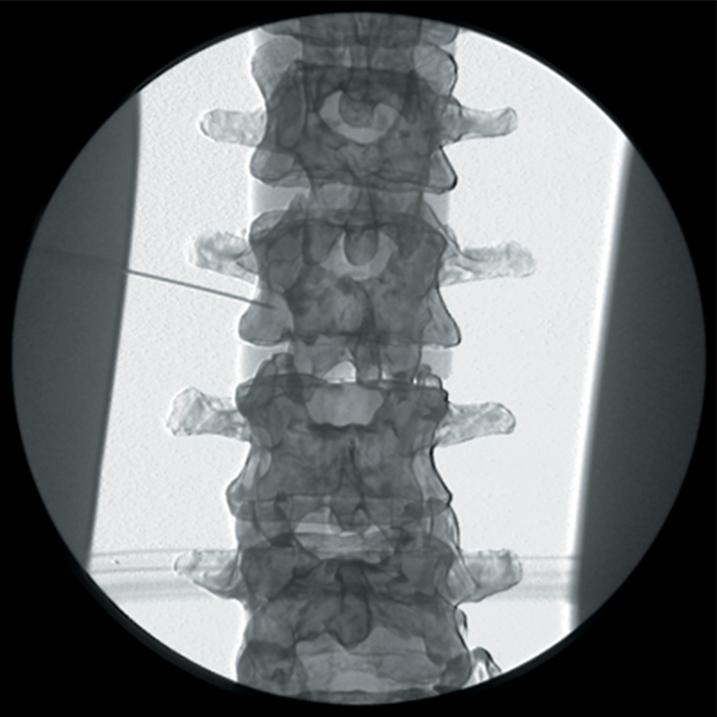

The Regional Anaesthesia Simulation Manikin has been designed by a Consultant Anaesthetist at the Manchester and Salford Pain Centre for training anaesthetists in correct needle placement in Nerve Blocks for pain management.

- Knowledge of surface anatomy applied to the individual nerve blocks

- Orientation of image and identification of appropriate radiographic landmarks

- Identification point of needle insertion and angle of direction

- Recognition of contact with deep bony structures

- Principle of withdrawing and directing needle to alter the angle

- The end point of simulation is the correct radiographic appearance

- Accurate needle placement is required to guarantee the efficacy of many diagnostic pain clinic blocks and is mandatory when neurolytic solutions are used. Radiological screening to confirm needle placement should be routine and training for this needs to be practical

- The manikin consists of a specially coated plastic human skeleton, head covered in artificial skin and fabric covered torso, on which trainees can practice the placement of needles under X-ray image intensifier control

- The X-ray density of the manikin is low so that the doses of radiation used during simulated procedures are reduced